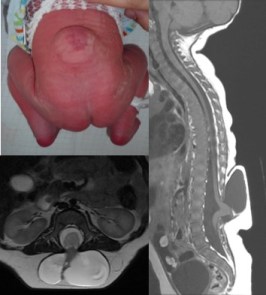

la myélocystocèle terminale

il s’agit d’une poche sacrée dans laquelle la moelle s’étale comme un pavillon de trompette, cette placode n’est pas fonctionnelle. l

e pronostic neurologique est favorable. en diagnostic anténatal, il importe de distinguer cette lésion, de bon pronostic, de la myéloméningocèle.